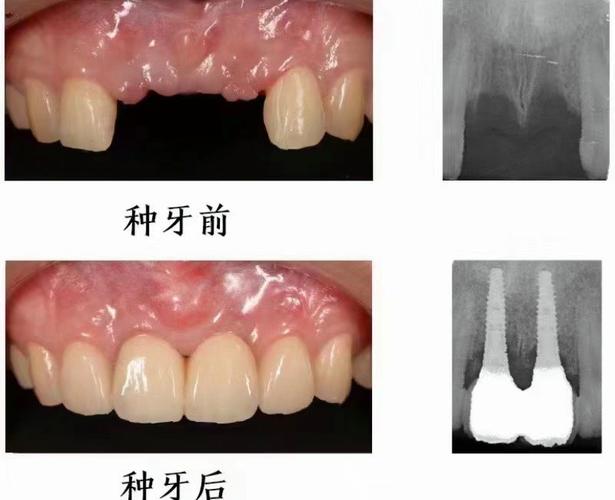

(图片来源网络,侵删)- 配备高端CBCT(锥形束CT),能精确评估牙槽骨情况,为种植方案设计提供关键依据。